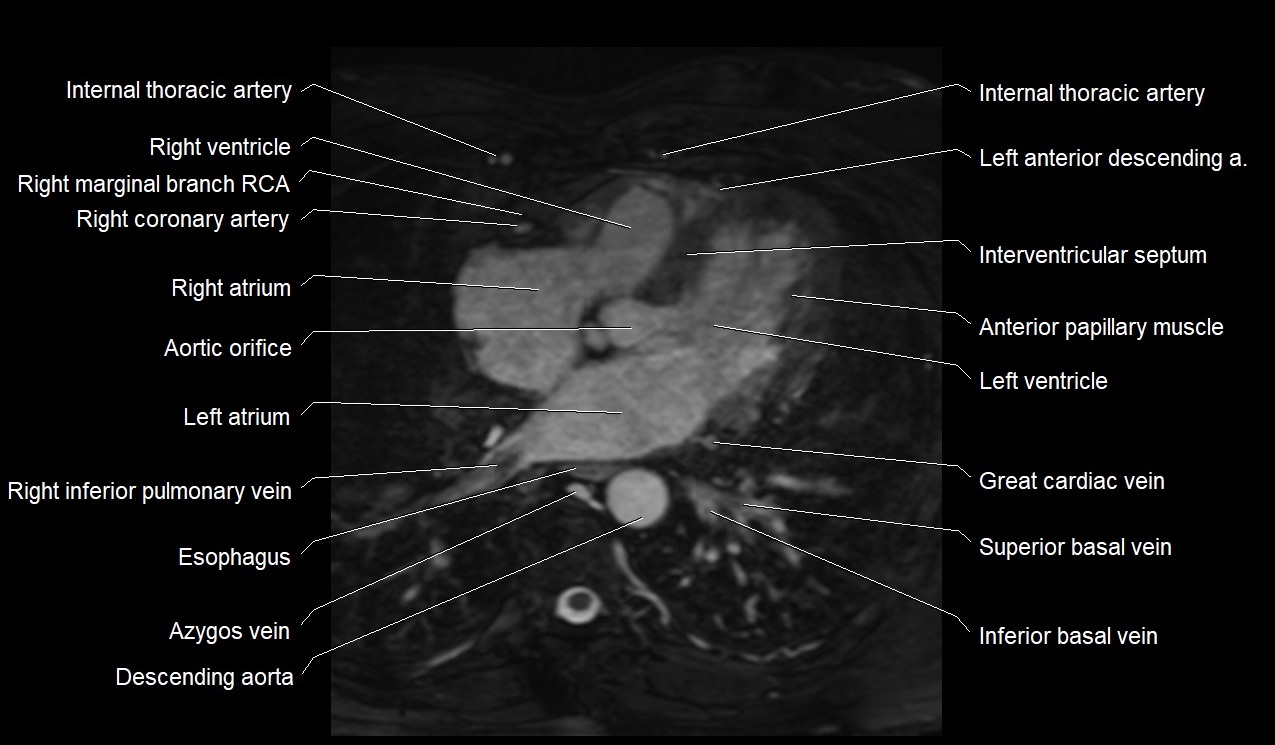

- Great cardiac vein

- Inferior vena cava

- Left atrium

- Left ventricle

- Right atrium

- Right coronary artery (RCA)

- Right ventricle

- Azygos vein

- Descending thoracic aorta

- Left anterior descending artery (LAD)

- Interventricular Septum

- Anterior papillary muscle